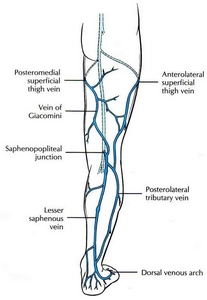

根據調查統計, 約有百分之25的女性, 和百分之18的男性, 罹患嚴重程度不等的靜脈曲張(varicose vein, vein reflux), 屬於慢性的文明病. 靜脈一般而言分成三種; 第一種乃深層靜脈(deep veins), 位於肌肉和纖維組織之間, 負責的靜脈血(也就是缺氧血, deoxygenated blood)的回流至心臟; 第二種是表淺靜脈(superficial veins), 位置在皮膚表層, 功能在收集表淺的血液; 第三種是穿透靜脈(perforator veins), 乃連接前兩種靜脈, 負責把表淺靜脈的血液帶到深層靜脈裏. 它的功能主要是把缺氧血帶回心臟

左圖可以知道各種靜脈的發生位置與相關

左圖可以知道各種靜脈的發生位置與相關